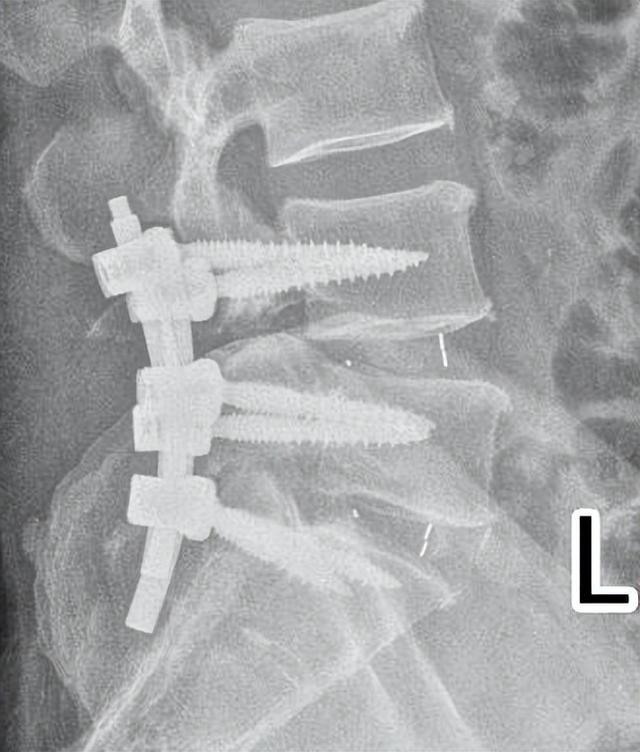

术后,唐先生腰背部疼痛及双下肢麻木的症状明显缓解,术后第10天开始佩戴支具下床锻炼,伤口愈合后,于11月9日顺利出院。

▲术后复查显示:内固定位置良好